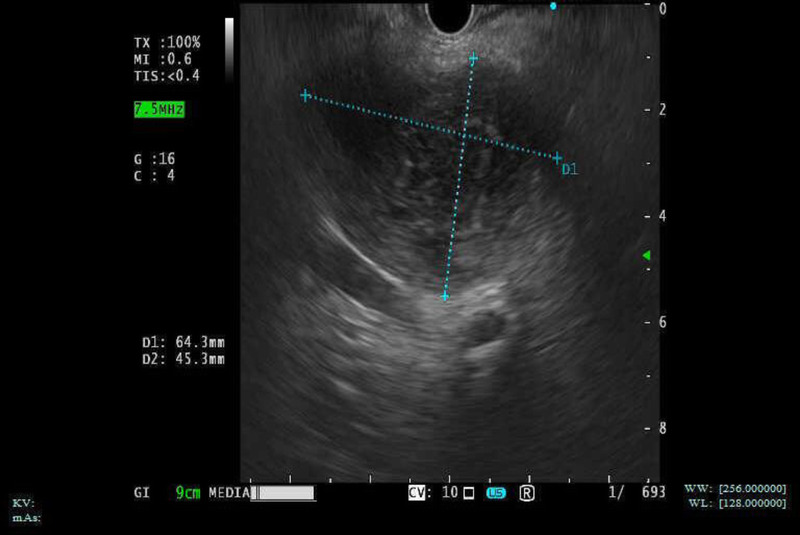

EUS-guided drainage of multidrug-resistant enterococcal caudate lobe abscess inaccessible with percutaneous approach (with video).